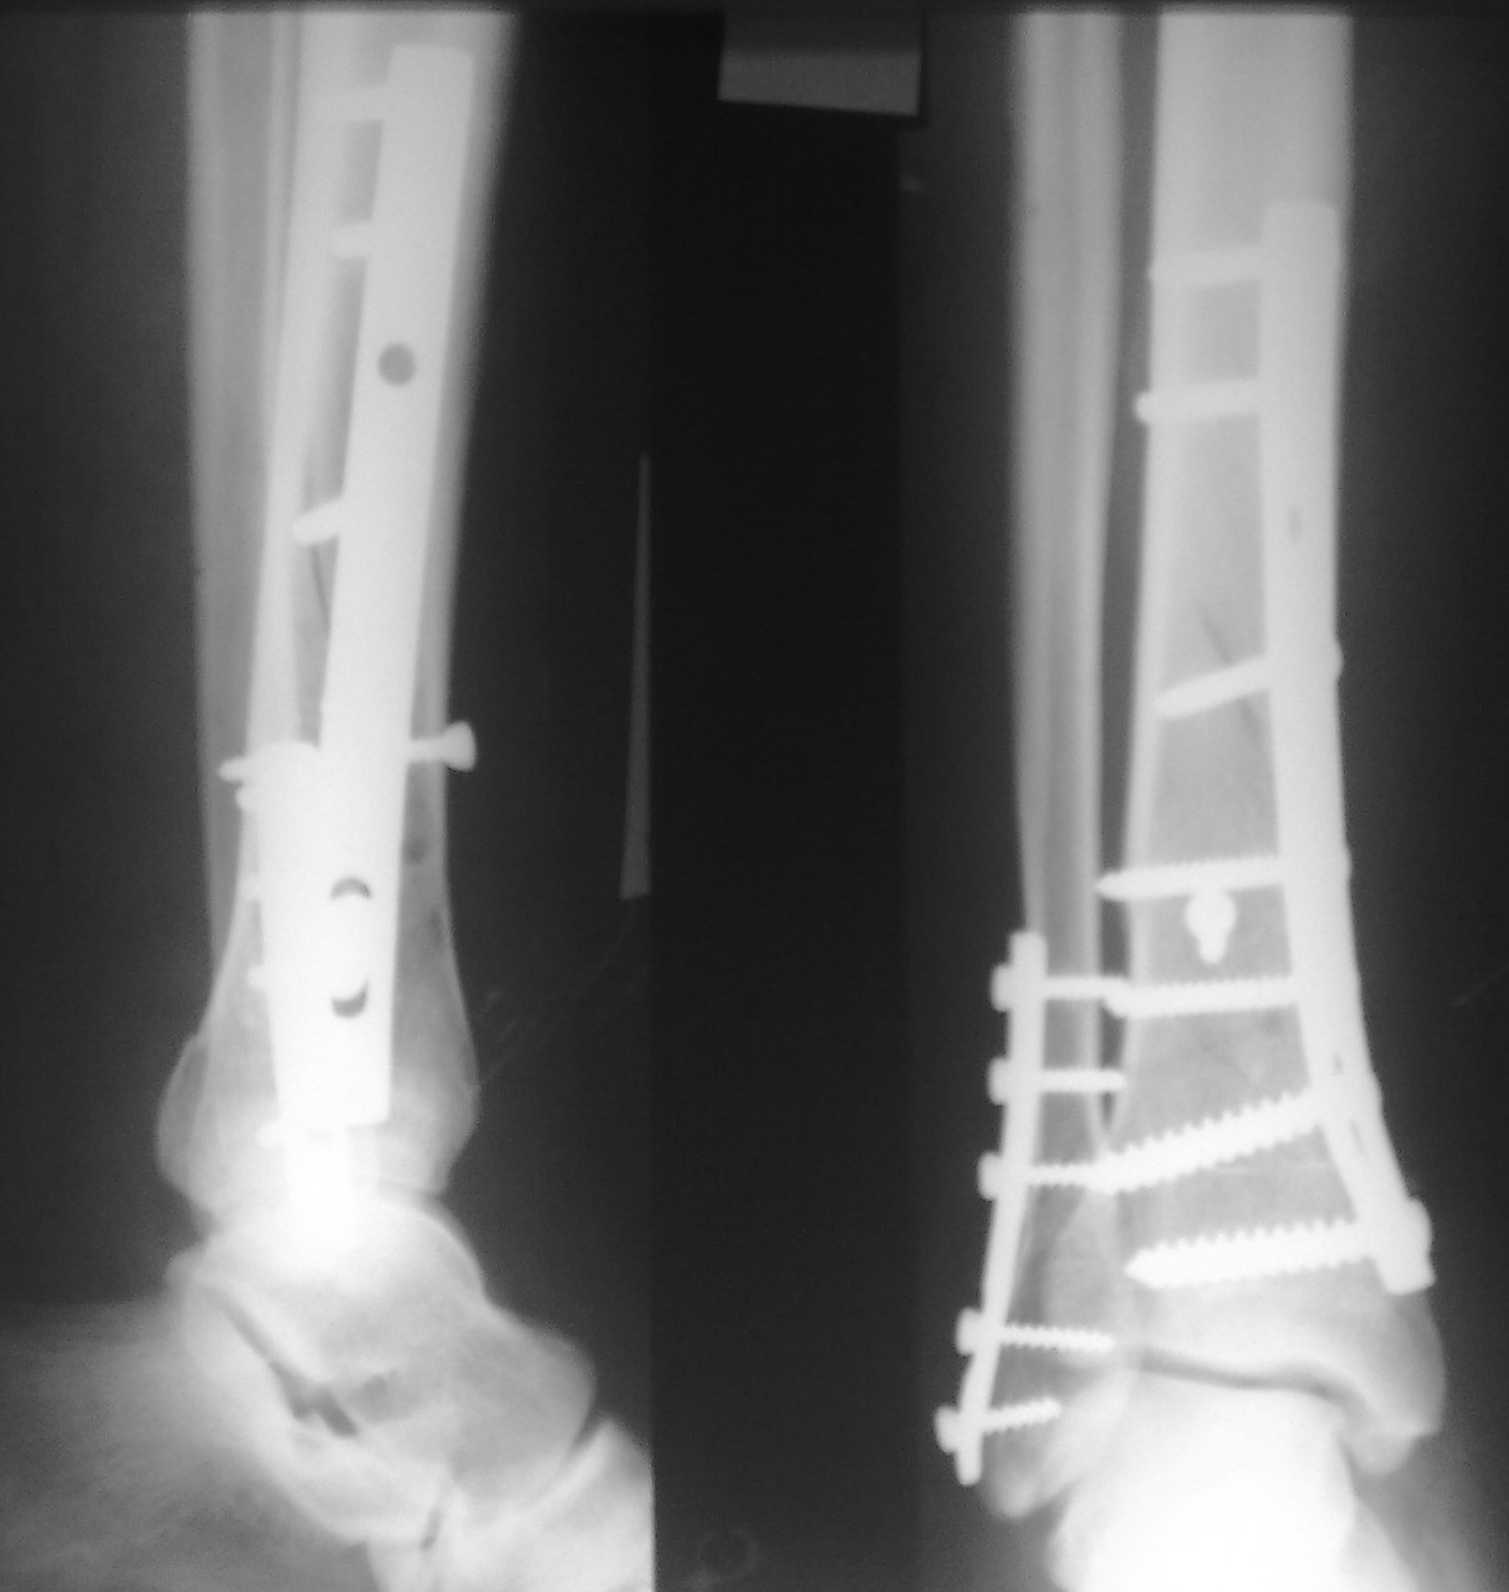

Спасибо за советы. Выполнен МОС обоих костей голени

По представленным послеоперационным снимкам создаётся впечатление сохраняющегося подвывиха + итраоперационно обнаруженный разрыв межкостной мембраны.

Извините за некачественные снимки и неправильную укладку в прямой проэкции. Подвывих рентгенологически не определяется. Кроме этого, после МОС малоберцовой кости интраоперационно однозубым крючком проверена стабильность синдесмоза - он стабилен. Кроме этого, интраоперационно проверена стабильность стопы в голеностопе - люфта ее при боковых отклонениях не определяется, также визуально при этом приеме отклонения малоберцовой кости кнаружи в ДМС не определяется. В дополнение к этому (у ассистента были сомнения) был сделан доступ к межберцовой связке и ее визуальный осмотр- она оказалась целой. При данных обстоятельствах позиционный винт мы не вводим.

Показания для остеосинтеза малоберцовой кости и наружной лодыжки при переломах голени и пилона известны и продолжают обсуждаться, литературу найти можно. Не вдавясь в подробности - в данном конкретном случае остеосинтез наружной лодыжки был желателен для ранней безболезненой реабилитации голеностопного сустава. Надобности в позиционном винте не было и быть не могло. Хочется только надеяться, что проведённая операция была достаточно доброжелательной к мягким тканям, хотя определённые детали послеоперационных Рентгенограмм могут косвенно свидетельствуют об обратном... Так же, как и достигнутая репозиция. Но это не входит в рамки обсуждения, насколько я понимаю. С уважением, Волна

Данная фиксация пластинами сделана классическим АО методом описанным еще в 1989 году в книге J. Mast и R. Ganz “Planning and Reduction Technique in Fracture Surgery”. В то время antiglade method DCP пластиной в 4.5 мм c повторением натурального изгиба голени в н/3 считался одним из оригинальных. Повторение оригинальной концепции и фиксация спонгиозными шурупами в дистальном отделе доказывает, что коллеги хорошо освоили метод АО. Но для уменьшения раздражения пластиной изнутри в нижнем отделе, авторы применяли технику погружения пластины в кортекс. Профилактические меры не всегда помогали, и в неумелых руках "передне-медиальный АО доступ" часто осложнялся кожными осложнениями.

Без современных материалов создать хорошую фиксацию становится трудной задачей, и этот случай характерен тем, что достигнутую идеальную репозицию испортили старомодной техникой. Исследования показали, что спонгиозные шурупы в метафизарных частях не создают механические преимущества как считали раньше. Кортикальные винты менее агрессивны и не оставляют дефекта кости после их удаления.

Низкопрофильные преконтурированные пластины с угловой стабильностью создают меньше проблем с медиальным покрытием, а толстая пластина становится раздражителем после спадения отека.